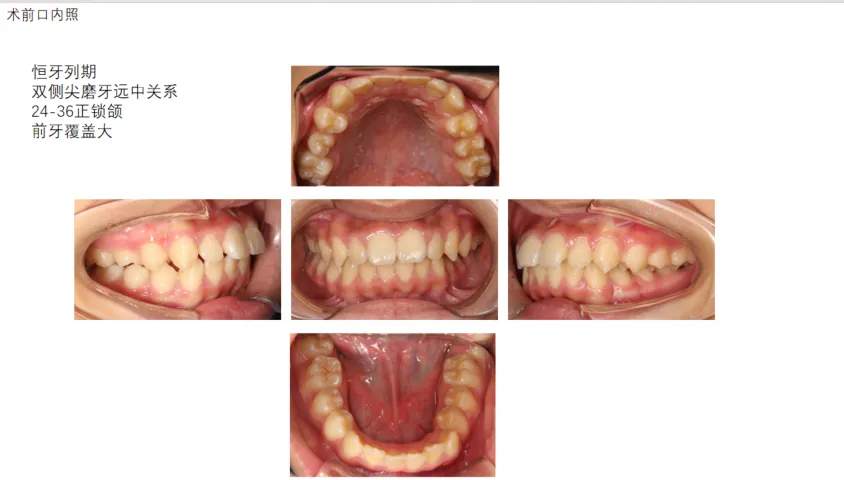

病例展示: